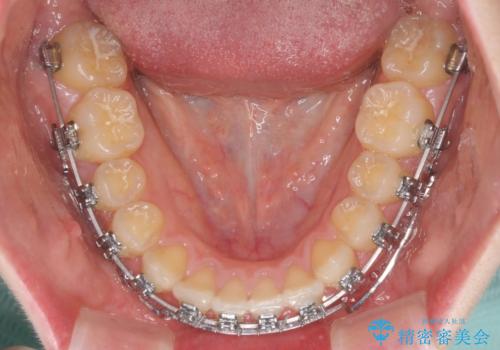

上顎のみの抜歯矯正 前歯のデコボコを改善する

- 矯正装置

- メタルブラケット

- 上顎前歯のデコボコを気にして来院された患者様です。

口元の突出感はなく、上顎のみに顕著な叢生が認められました。

上顎の左右第一小臼歯2本を抜歯し、ワイヤー装置にて歯列を整えることとしました。

奥歯の咬み合わせがなかなか定まらず、スペースが閉じるまでに時間がかかりましたが、最終的には正中を合わせることもできました。